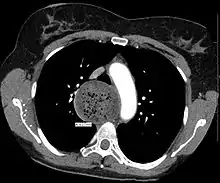

![]() | |

| A chest X-ray showing achalasia ( arrows point to the outline of the massively dilated esophagus ) | |